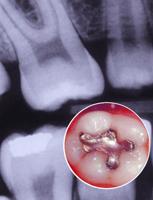

银汞合金(amalgam)是一种特殊类型的合金,可由汞与一种或多种金属形成。用于牙体修复的汞合金是一种历史悠久的牙科充填材料,我国苏恭著《唐本草》(公元659年)中就有银膏的.记载。李时珍所著的《本草纲目》(公元1578年)对此进行了更加详细的描述。1896年国C.V.Black对银汞合金的组成、性质、调和及充填方法进行了大量的研究和改进,使银汞合金逐渐成为较理想的充填材料。目前尽管治疗龋病的充填材料甚多,但后牙的充填,尤其是牙合力较大的洞形还没有比银汞合金更为优越的充填材料,据统计,银汞合金在后牙牙体修复中占全部牙体修复的80%,有长达10-30年的临床寿命。

电子显微探针X线图像法可观察到银汞合金的内在结构、各种金属的组成成分,还可以分析出各种成分的含量。用这种方法观察普通合金,可见到银锡相(r相)、银汞相(r1)及锡汞相(r2),其中有空泡及裂隙,究其原因与r2相有关,此相可形成氯化锡、锡—氧—氯或锡氧等。

这与临床上出现的腐蚀现象有关,进而使充填体的边缘及本体折断,造成继发龋等。

MarchallCW等观察充填后10年的普通合金及高铜合金充填体或充填体碎块,证实普通合金有许多成孔部位,特别是深处,其中充满氯化锡,而高铜合金腐蚀产物仅在表面及少数孤立区存在成孔部位。